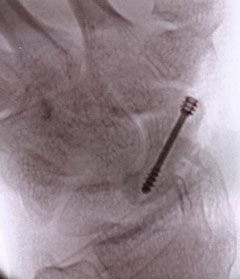

Percutaneous technique. Used for minimally displaced fractures, this technique is not suitable for all fractures. Through a 4mm stab incision and x-ray guidance a screw is passed into the bone. Because less soft tissues are cut the recovery is quicker and a plaster is only needed for 10-14 days.